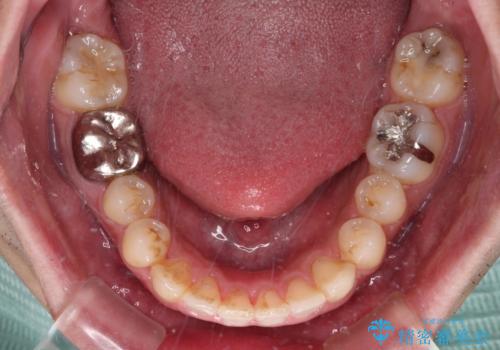

前歯のデコボコと突出感をマウスピース矯正できれいに

- 上下前歯のデコボコと突出感を気にして来院された患者様です。

目立たない装置を希望されたため、インビザラインによるマウスピース矯正を行うこととしました。

矯正治療後に銀歯をセラミックに替えたいとの要望があり、概ね歯列が整ったところで銀歯をセラミックに替え、仕上げにインビザライン1セットを使用して最終的に歯列を整えました。